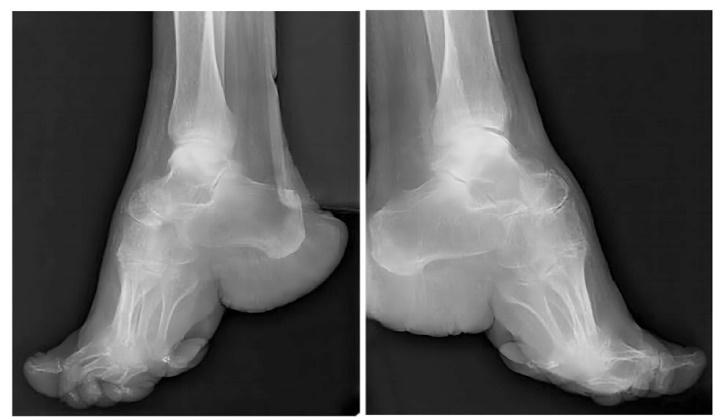

| [5] | Michael LR. Chinese foot binding: Radiographic findings and case report.[J]. Radiology Case Reports, 2009, 4(1): 270 |